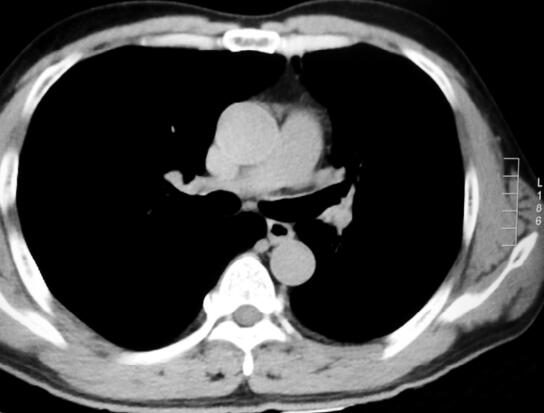

支气管肿物首先用电圈套器切除大部分,然后应用冷冻切除,肿物几乎被完全切除,左上叶支气管及左舌叶支气管清晰显示。复查胸部CT左主支气管管腔通畅(图2)。患者术后咳嗽、咳痰症状明显缓解。再次送检病理结果,肿物内可见混有成熟软骨、平滑肌组织,病理报告为错构瘤(图3HE×40)。

图2